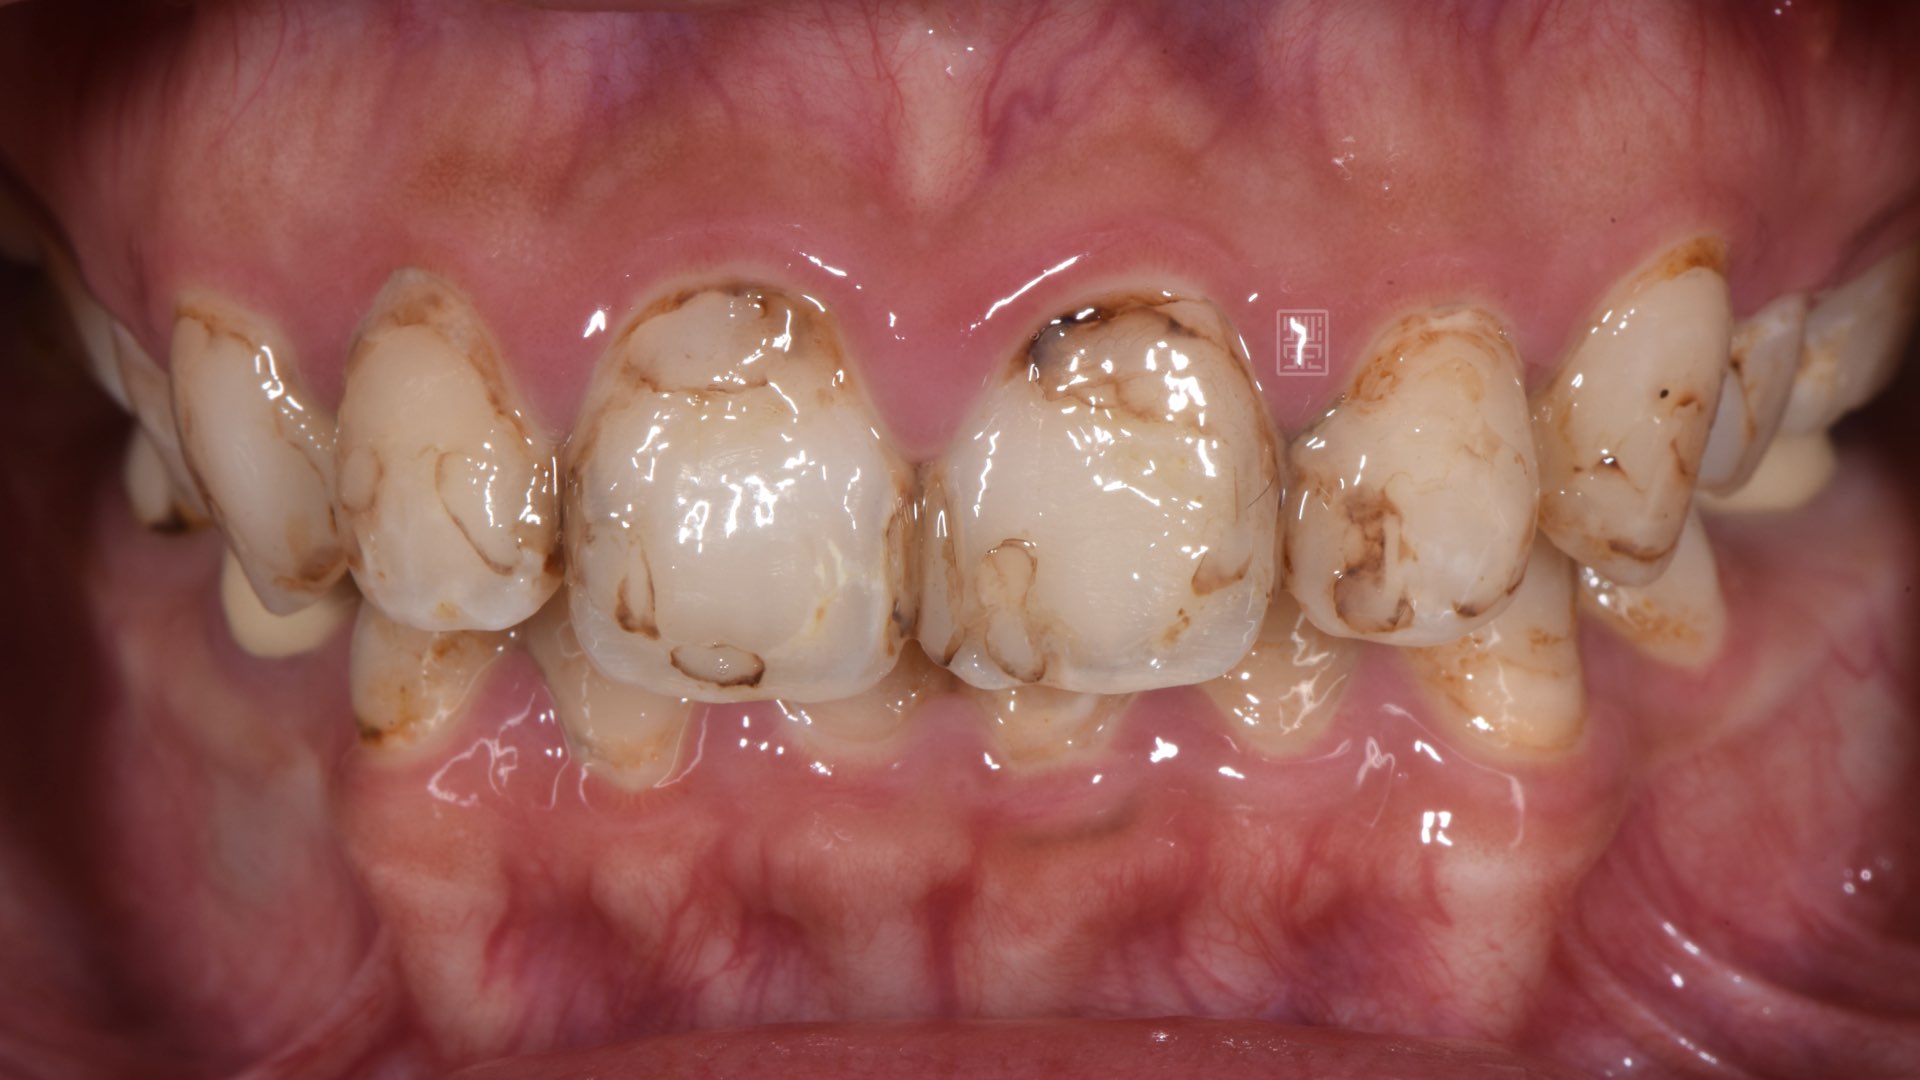

陳小姐覺得自己的牙齒黃、比較暗沈,加上小時候補牙的痕跡明顯,多年來,牙齒多次樹脂填補治療,顏色都不均勻,到榮醫師的門診檢查後發現,過去多次的蛀牙治療,許多牙位都損傷嚴重。

門齒多次蛀牙填補

門齒蛀牙清除

重新樹脂填補完畢,門齒比例80%,不宜做牙冠增常術